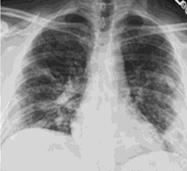

Стандартная РГ имеет низкую чувствительность в выявлении начальных изменений в первые дни заболевания и не может применяться для ранней диагностики. Информативность РГ повышается с увеличением длительности течения пневмонии. Рентгенография с использованием передвижных (палатных) аппаратов является основным методом лучевой диагностики патологии ОГК в отделениях реанимации и интенсивной терапии (ОРИТ). Применение передвижного (палатного) аппарата оправдано и для проведения обычных РГ исследований в рентгеновском кабинете. В стационарных условиях относительным преимуществом РГ в сравнении с КТ являются большая пропускная способность. Метод позволяет уверенно выявлять тяжелые формы пневмоний и отек легких различной природы, которые требуют госпитализации, в том числе направления в ОРИТ.

КТ имеет высокую чувствительность в выявлении изменений в легких, характерных для COVID-19. Применение КТ целесообразно для первичной оценки состояния ОГК у пациентов с тяжелыми прогрессирующими формами заболевания, а также для дифференциальной диагностики выявленных изменений и оценки динамики процесса. КТ позволяет выявить характерные изменения в легких у пациентов с COVID-19 еще до появления положительных лабораторных тестов на инфекцию с помощью методов амплификации нуклеиновых кислот. В то же время, КТ выявляет изменения легких у значительного числа пациентов с бессимптомной и легкой формами заболевания, которым не требуется госпитализация. Результаты КТ в этих случаях не влияют на тактику лечения и прогноз заболевания при наличии лабораторного подтверждения COVID-19. Поэтому массовое применение КТ для скрининга асимптомных и легких форм болезни не рекомендуется.